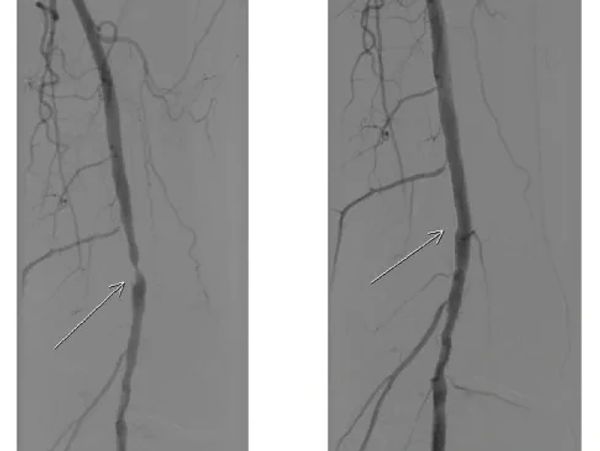

A peripheral angiogram is an imaging test used to evaluate the blood vessels in your limbs. During the procedure, a contrast dye is injected into your arteries, and X-ray images are taken to show how blood is moving through the vessels. This test helps identify:

- Gives you a clear picture of blood flow in your arms or legs

- Pinpoints the exact location and severity of blockages